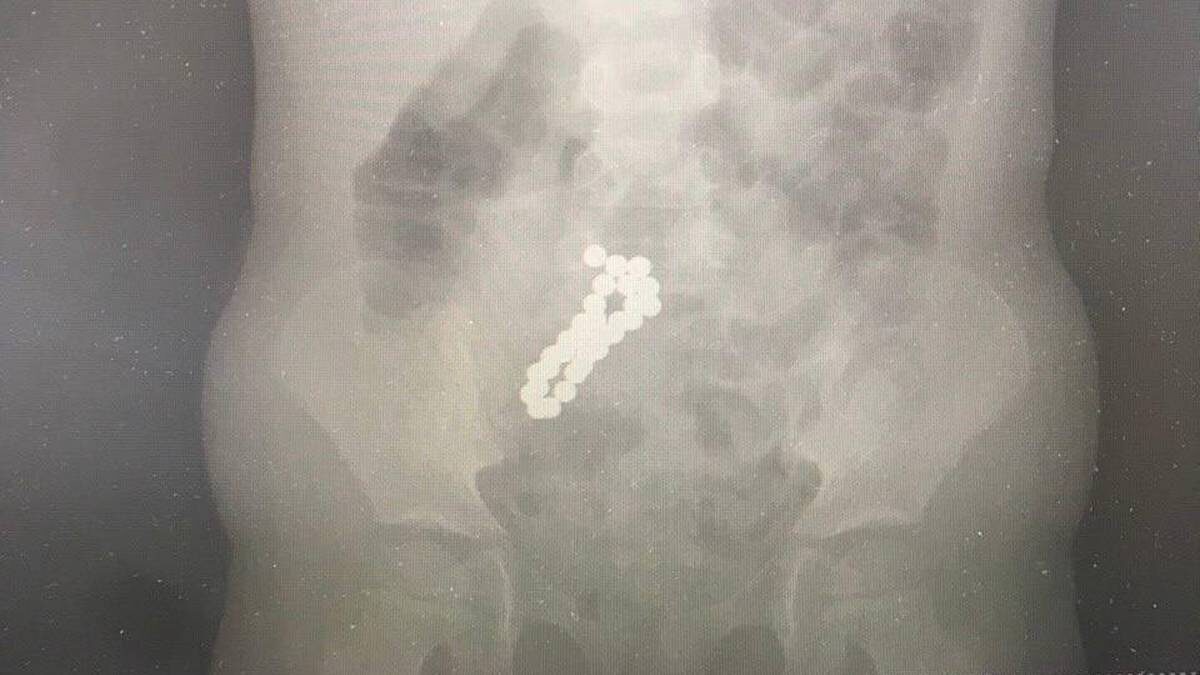

Специалисты Московского областного центра охраны материнства и детства (МОЦОМД) достали из кишечника четырехлетней девочки 30 магнитов. Об этом во вторник, 3 марта, сообщили в пресс-службе регионального министерства здравоохранения. Родители ребенка вызвали скорую помощь, так как у девочки наблюдалась сильная рвота. Ранее они обнаружили, что из дома бесследно пропал магнитный конструктор. — Врачи провели исследования и обнаружили в тонком кишечнике девочки 30 магнитных шариков диаметров по десять миллиметров. Магниты извлекли лапароскопически — через маленькие проколы, — объяснил врач детского хирургического отделения Сергей Борисов. Операция прошла успешно, состояние ребенка сразу же улучшилось. Сейчас девочка уже лечится дома, уточнили на сайте ведомства. Ранее врачи ГКБ имени Буянова спасли девушку, у которой дважды остановилось сердце. Пациентке стало плохо дома во время просмотра телевизора: ей сдавило грудь, после чего она потеряла сознание. Скорую вызвал ее супруг. Эксклюзивы "В

Фото: Пресс-служба Министерства здравоохранения Московской области

— Врачи провели исследования и обнаружили в тонком кишечнике девочки 30 магнитных шариков диаметров по десять миллиметров. Магниты извлекли лапароскопически — через маленькие проколы, — объяснил врач детского хирургического отделения Сергей Борисов.